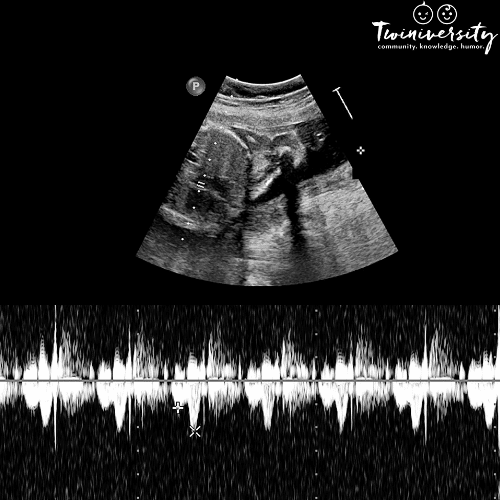

Aside from that first cry, there is no sweeter sound than when you hear your twins’ heartbeats for the first time. Whether you found out it was twins right away, or an ultrasound showed you later in your pregnancy, you’ll be eager to hear those two heartbeats thump-thumping together. You might be wondering when and how this happens, and if having twins will change your experience. We’ve got you covered with all you need to know about this important milestone of twin pregnancy.

A baby’s cardiac muscles begin to develop between weeks 3 and 5 of pregnancy. As the heart chamber develops, a flickering beat can be seen by transvaginal ultrasound as early as 3 to 4 weeks gestation, and a regular ultrasound between weeks 6 and 8. Finally, around week 10 the babies’ heartbeats are usually strong enough to hear with a fetal Doppler or ultrasound. Around week 20, the heartbeats can be heard through a stethoscope.

A fetal Doppler is a monitoring tool used by your doctor or midwife as part of your routine prenatal care. This device works like an ultrasound as it uses sound waves to detect a baby’s heartbeat. However, it only transmits sound. Beginning with your 10 to 12 week prenatal appointment, your care provider will perform a fetal Doppler test with each check-up. This is to ensure the babies’ heart rates are strong and normal. An identical twin pregnancy may have more frequent ultrasounds. However, it is common in diamniotic (fraternal) pregnancy to rely on the fetal Doppler test during the first and second trimesters. A fetal Doppler test is completely safe and painless with the ultimate reward of hearing the pitter-patter of your womb.

To perform a fetal Doppler test, the pregnant person lies down and the physician applies gel to a probe. This gel acts as a conductor for the sound waves. They then guide it along the abdomen until they encounter fetal heart sounds. Once a fetal heartbeat is located, you can hear the sound through a speaker on the main unit of the fetal Doppler. While listening for healthy heart sounds, your doctor will also count each baby’s beats per minute (BPM) as an indication of their health and development.

During a fetal Doppler test or ultrasound, you will hear a few different sounds coming from your bump. In general, you’ll hear a repetitive “whooshing” noise, which is the fetal blood flow through the umbilical cord. Some pregnant people refer to it as a wave sound. You’ll know when the Doppler is directly over a baby’s heart as you’ll hear a very quick clippity-clop rhythm. Many expectant parents have described it as a thundering train or a horse galloping. Most parents agree it’s a magical experience that makes it all feel real.